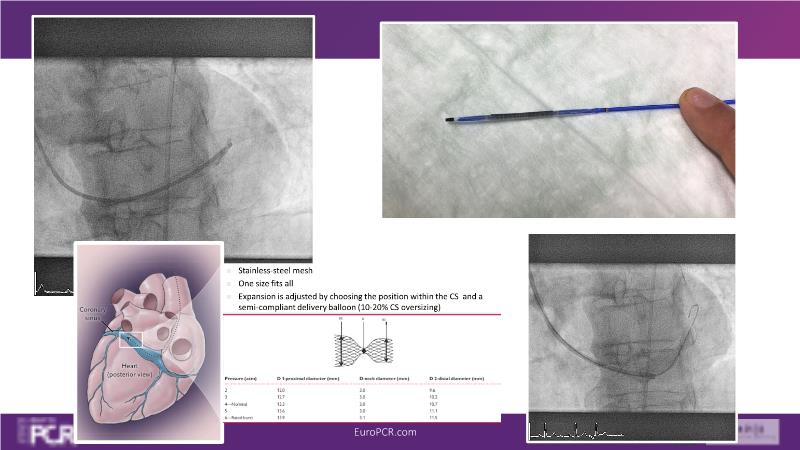

Watch this session to learn how Sinus Reducer may relieve angina by increasing pressure in the coronary sinus, and how it was associated with significant improvement in symptoms and quality of life, as long as the different steps of this simple procedure are dully followed and respected.

- To understand the mechanism of action of coronary sinus Reducer for the treatment of refractory angina

- To uncover practical tips and techniques to use coronary sinus Reducer in your practice